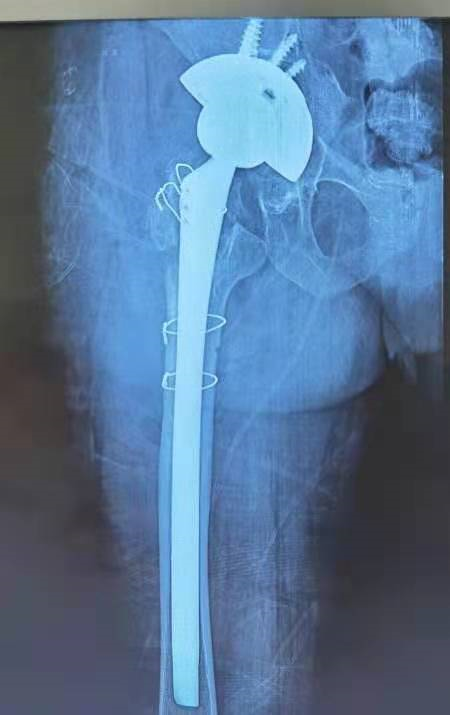

术后X线: